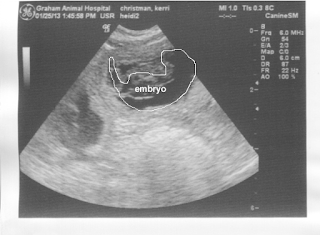

Can

you see the resemblance to the National Geographic image above?

At this stage, the puppies’ eyes and spinal cords have begun

to develop and the face is also forming. Fetuses are approximately 1.3 cm.

This may seem small but they will triple in size in just one week. Between days

29 and 35, their toes, whiskers and claws start to develop. They are now beginning to look like dogs! Interestingly, their

eyes are initially open but their eyelids fuse at around day 35 to protect them

from contamination during development and remain closed until approximately 10

days after birth.